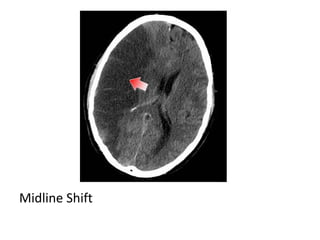

b) Generalized Mass Effect :

-Ventricular or basal cistern effacement +/-

midline shift (subfalcine herniation) or other

herniation syndromes : uncal , transtentorial

Midline Shift